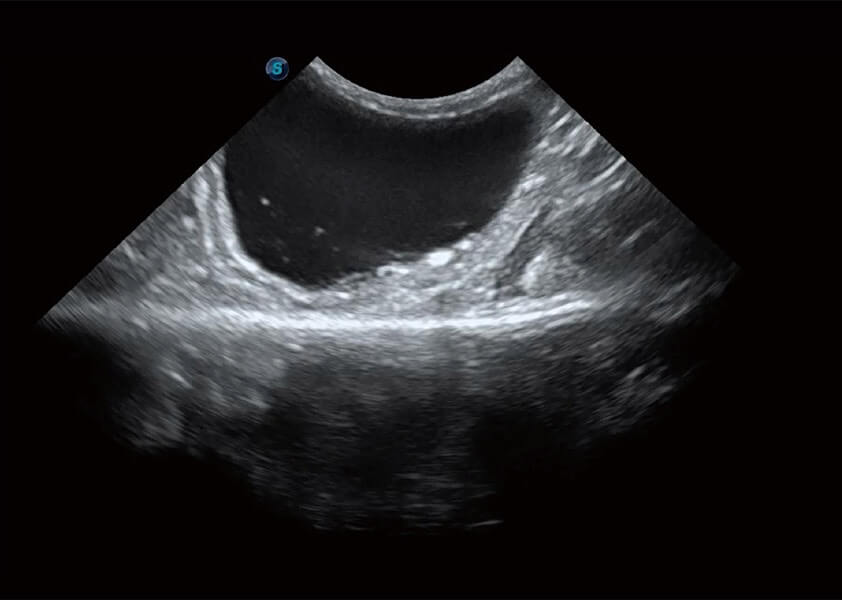

ProPet 60 作為一款高端臺式動物超聲設(shè)備,為動物醫(yī)生的日常診斷提供了一系列貼合動物臨床需求、解決臨床實(shí)際問題的高級成像功能。憑借全系列高清探頭,滿足醫(yī)生對腹部、心臟、生殖、淺表、肌骨等成像的所有需求,切實(shí)幫助您提升檢查效率,提高診斷信心。